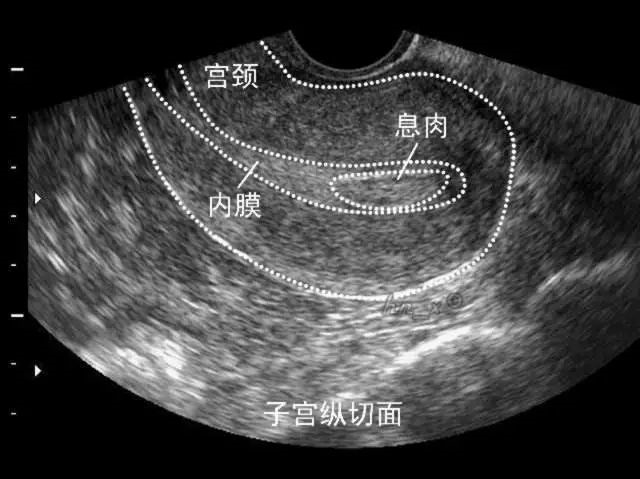

卵泡大小意味着什么呢?、图为超声波显现的子宫。可以了解子宫内膜的厚度和有无疾病。